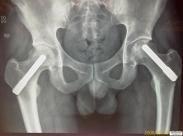

• 特發性股骨頭壞死

特發性股骨頭壞死又稱為缺血性股骨頭壞死,是一種常見病,股骨頭壞死的病因多種多樣,但其共同的病理機制是骨組織缺血,所以關于發病機制、血供受阻理論最易被人接受。這種...